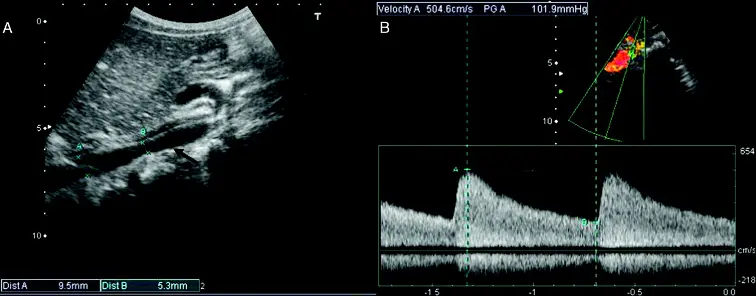

- Coarctation of aorta for abdominal aorta U/S will be flipped (i.e. positively oriented) and less prominent (as your measuring further away from the coarctation), but similarly won’t return back to baseline